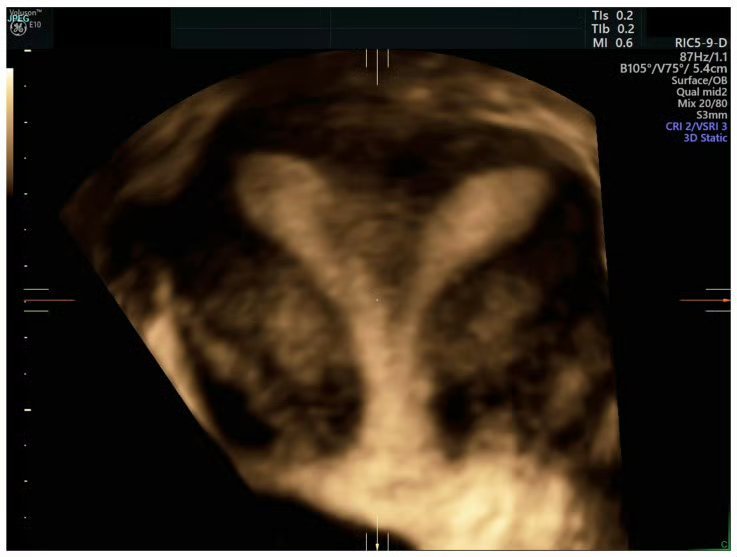

女子罕见双子宫双阴道10年3次剖宫产¹ 兔子就有两个独立的子宫。极少数人类女性有两个子宫,中间有纵向隔膜。很多可以自然受孕、生育。² 图1:26岁,两个子宫, 左右各一。³ 男的也可能有两根阴茎。热点科普